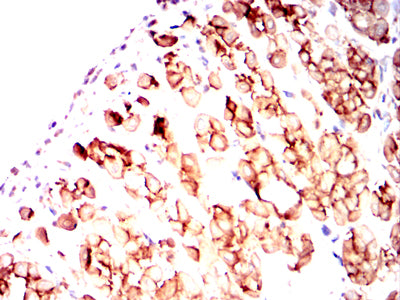

Product Image |

|